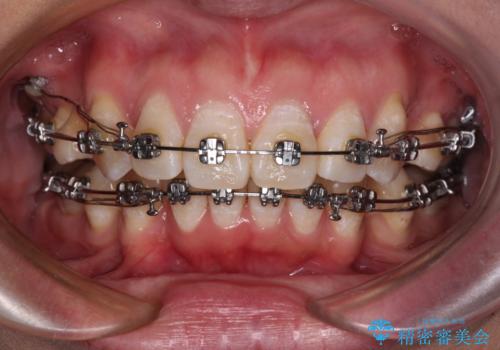

- メタルブラケット

- 2年6ヶ月

骨格的に上顎歯列が前方位にあり、口元の突出感が顕著な状態で、上下左右の第一小臼歯4本を抜歯して、ワイヤー装置での抜歯矯正を行うこととしました。

奥歯の咬み合わせ改善のために、アンカースクリューの使用と上顎左右第一小臼歯の抜歯のタイミングをコントロールして、理想的な咬み合わせに仕上げていくこととしました。